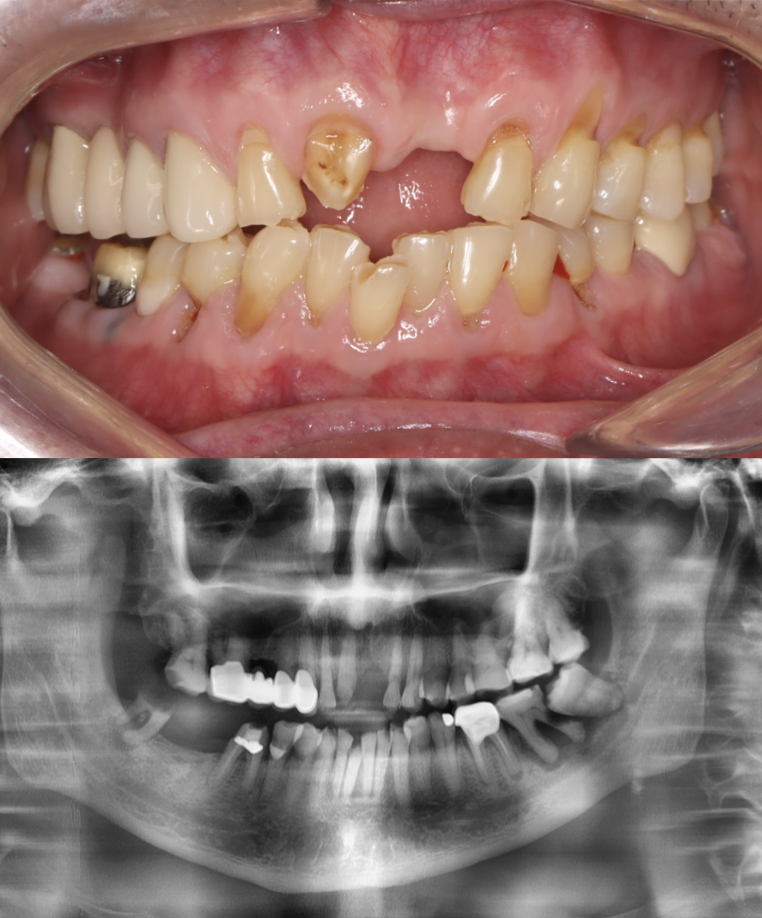

Before

After

All-on-6 implant

This All-on-6 implant case was performed on a patient with severe periodontitis. Implants were placed with immediate loading, allowing the patient to receive a temporary prosthesis right after surgery. The final fixed prosthesis was delivered 4 months later, restoring full function and esthetics. Treatment completed at Moral Dental Clinic.